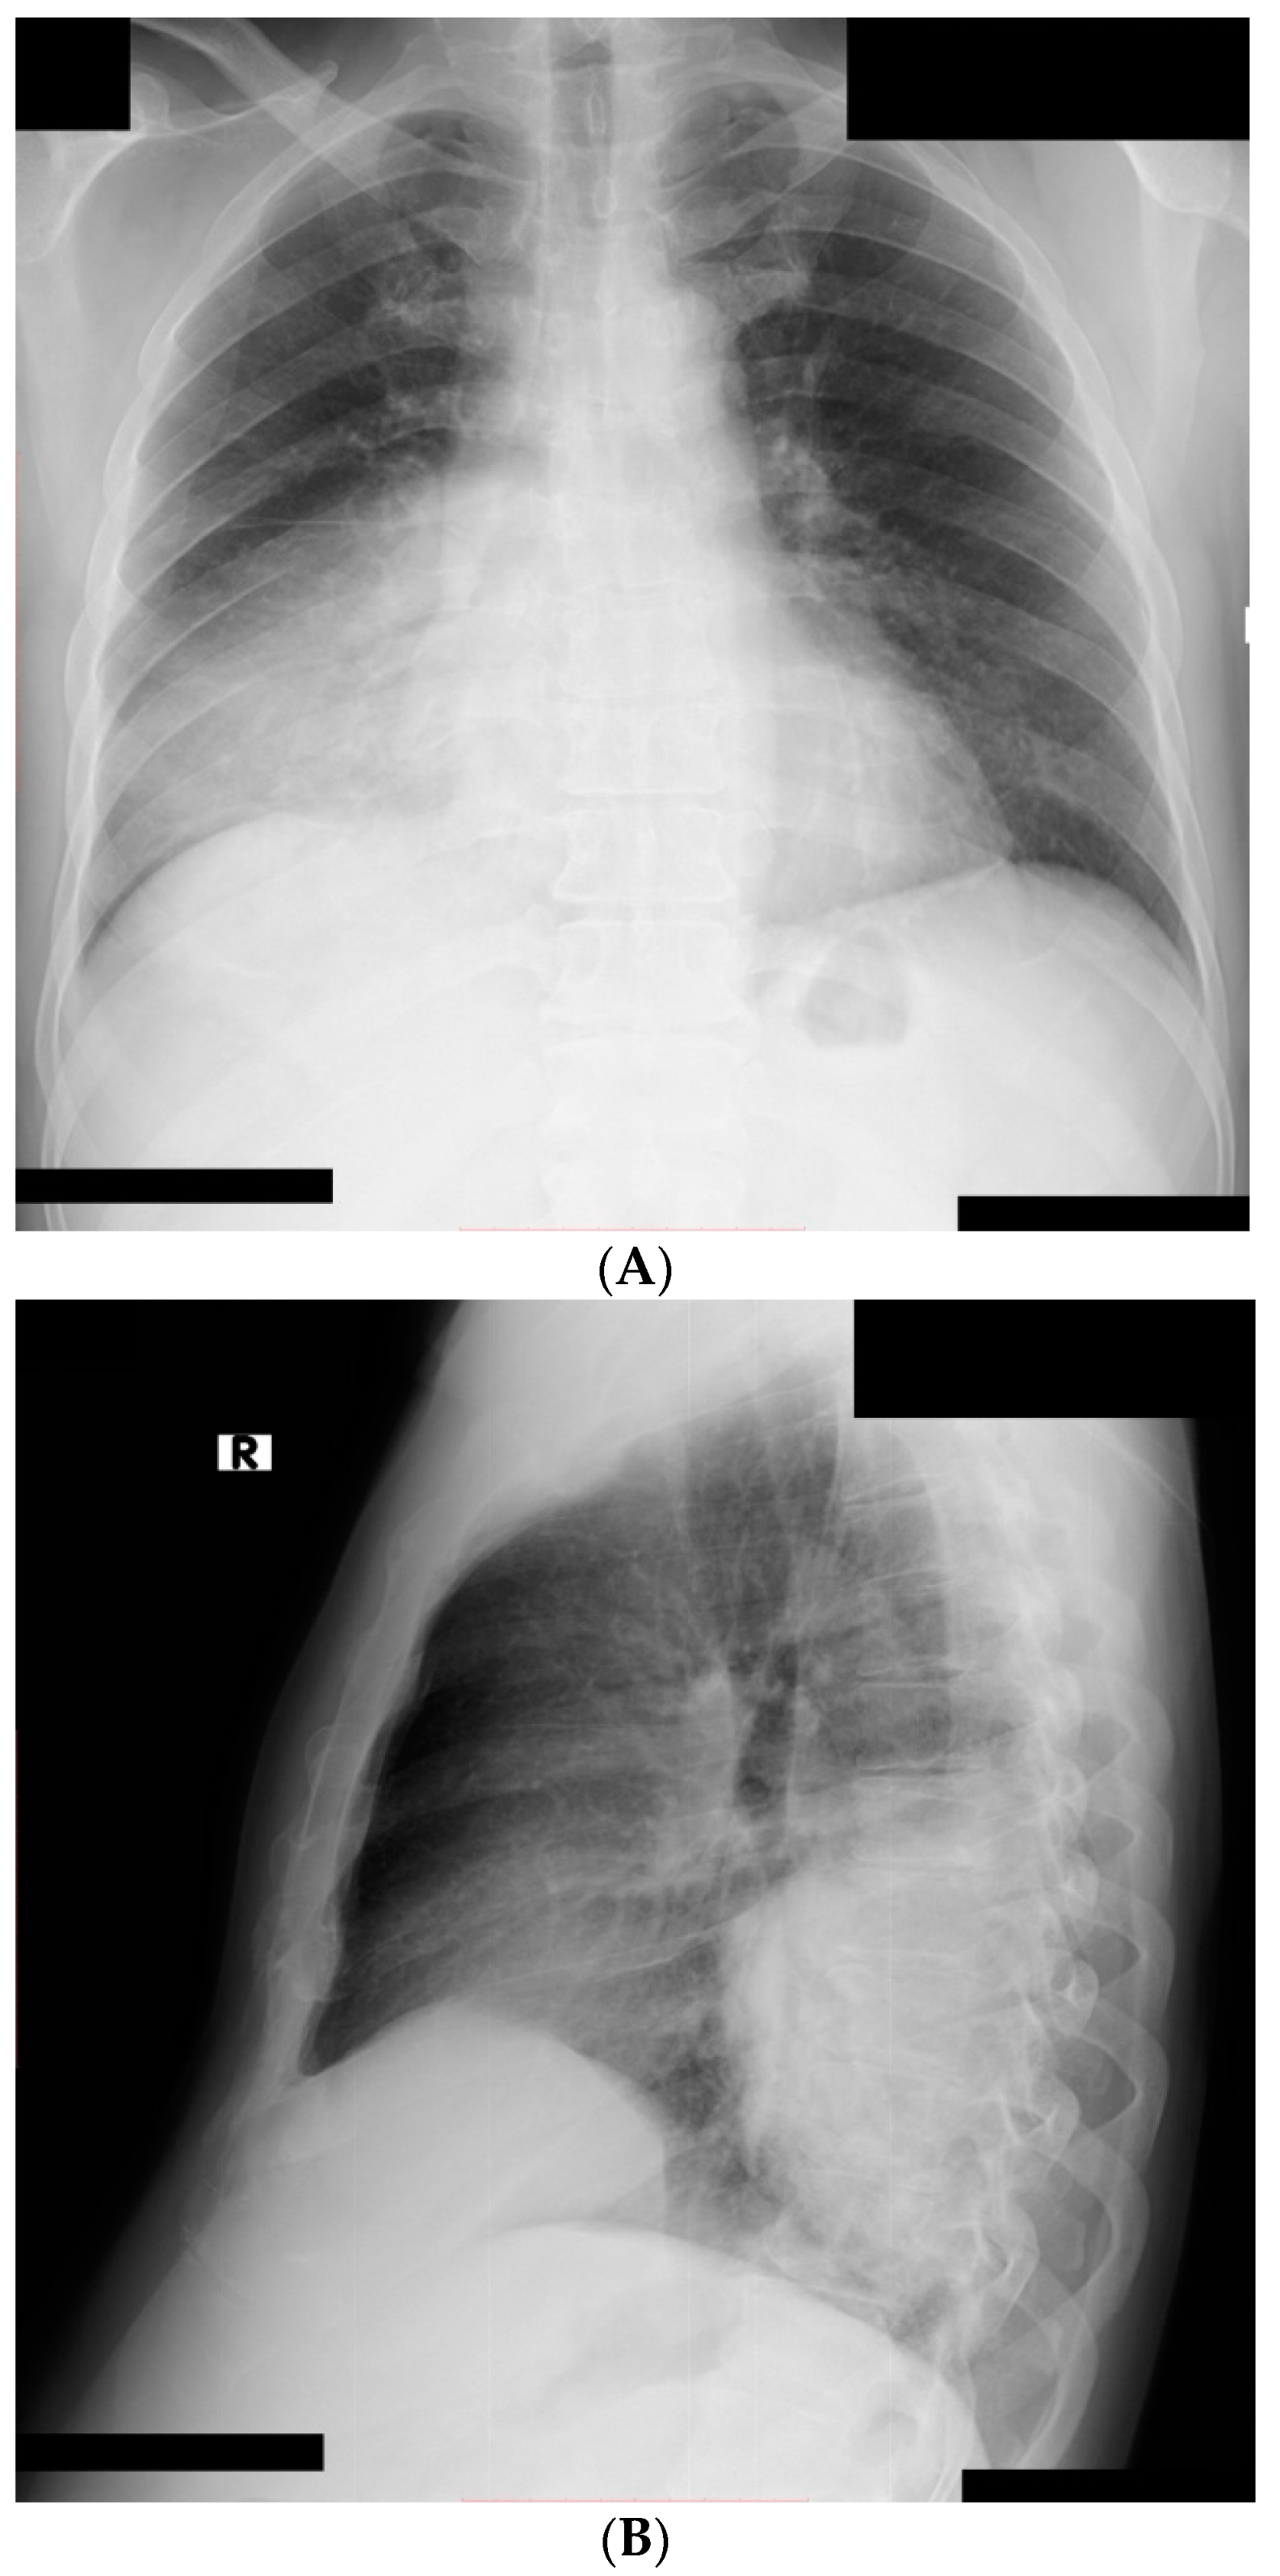

2. Case Presentation